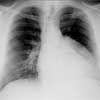

Chest films are ordered.

Chest radiographymay reveal such diagnostic features as: